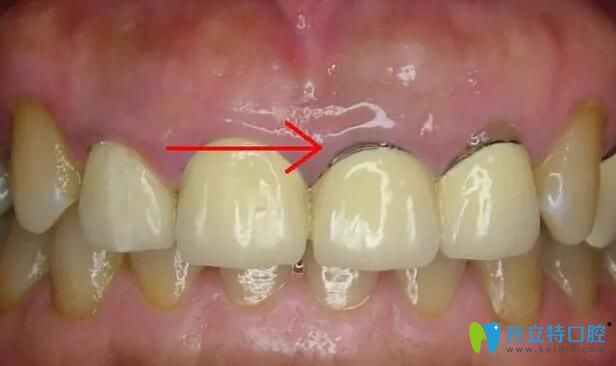

1、比較常見(jiàn)的牙齦黑線:這是鎳鉻烤瓷牙和鈷鉻烤瓷牙比較常出現(xiàn)的情況,這是因?yàn)閮?nèi)冠的非貴金屬材料在口腔內(nèi)氧化變成的灰色氧化物,時(shí)間長(zhǎng)了就會(huì)沉淀在牙齦上。如果不及時(shí)拆除,有可能會(huì)出現(xiàn)牙周炎、牙齦炎嚴(yán)重的也會(huì)導(dǎo)致牙齒脫落。

烤瓷牙牙齦黑線